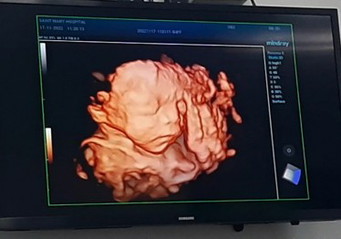

อัตเดตน้องค่ะแม่ๆ วันนี้หมอนัดตรวจอัลตร้าซาวด์ อายุครรภ์ตอนนี้ 10w3d ค่ะ เห็นน้องแล้วค่ะ ตอนตรวจอายุครรภ์ 7w4d ความยาวน้อง 1.31cm ปัจจุบันน้อง 3.57 cm ค่ะ หมอบอกหัวใจน้องเต้นแล้วปกติ น้องกำลังหลับอยู่🥰😁 #ใบอัลตร้าซาวด์แม่ๆบางคนเห็นตัวน้องชัดแจ๋วเลยของเราเป็นเพราะหนังท้องหนาหรือเครื่องตรวจคุณหมอหรือเปล่าคะ😅